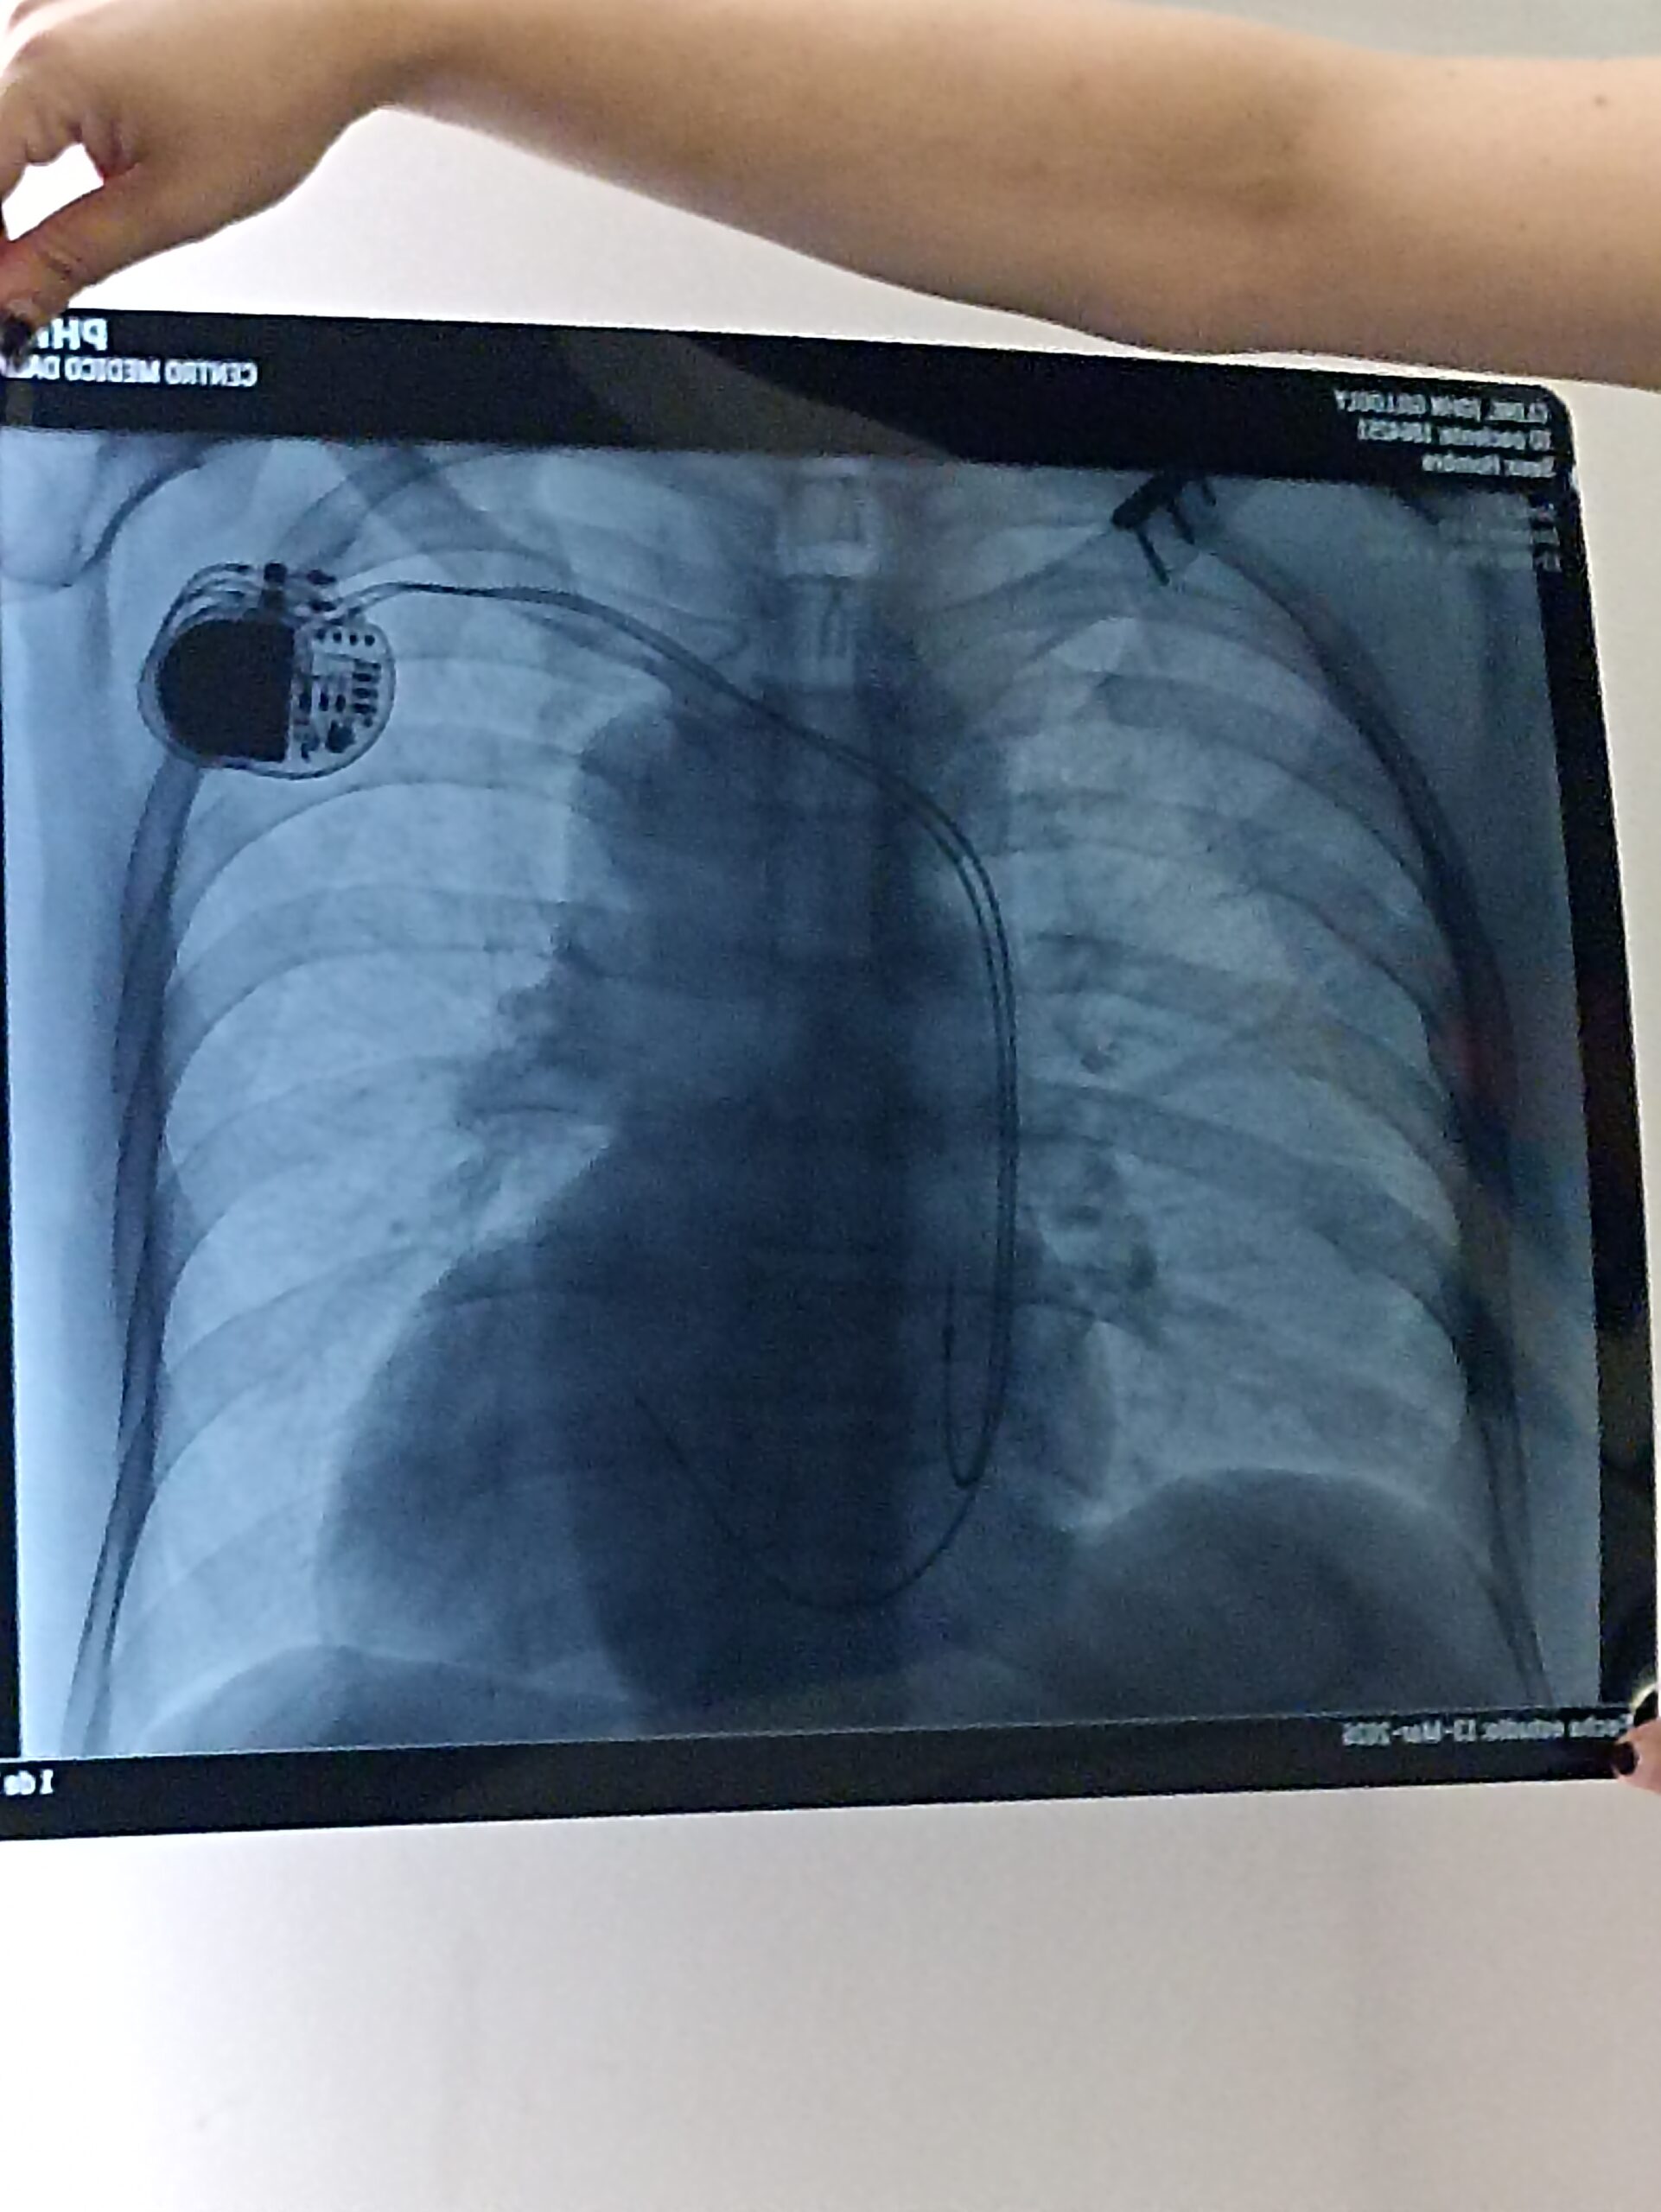

I woke up four weeks ago and logged into a meeting and my body was not happy and almost passed out. I went to the ER and was diagnosed with 3rd degree heart block and hypertrophy cardiomyopathy.

In a nutshell, I had a pacemaker installed while there and have been in recovery ever since.